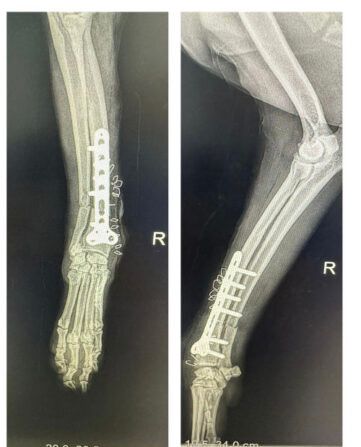

Last week, the hospital performed an orthopaedic surgery on a cat with a fractured leg. In cases like these, veterinarians perform bone pinning and bone plating just like in humans.

The surgical methods help fix broken legs by using pins or metal plates to hold the long bone in place, allowing it to heal properly and regain strength.

“In dogs and cats, the major surgery we provide is in the field of orthopaedic surgery, which includes the intermediary bone pinning and bone plating in terms of long bone fractures. For gastrointestinal surgery, the common condition in pets, let it be dog or a cat, is mainly a foreign body injection. So, sometimes there is a condition called intussusception where one intestine goes into the other intestine. So, in terms of gastrointestinal, we provide gastrotomy surgery,” said Dr Nima Wangdi, Deputy Chief Veterinary Officer, National Veterinary Hospital, Thimphu.